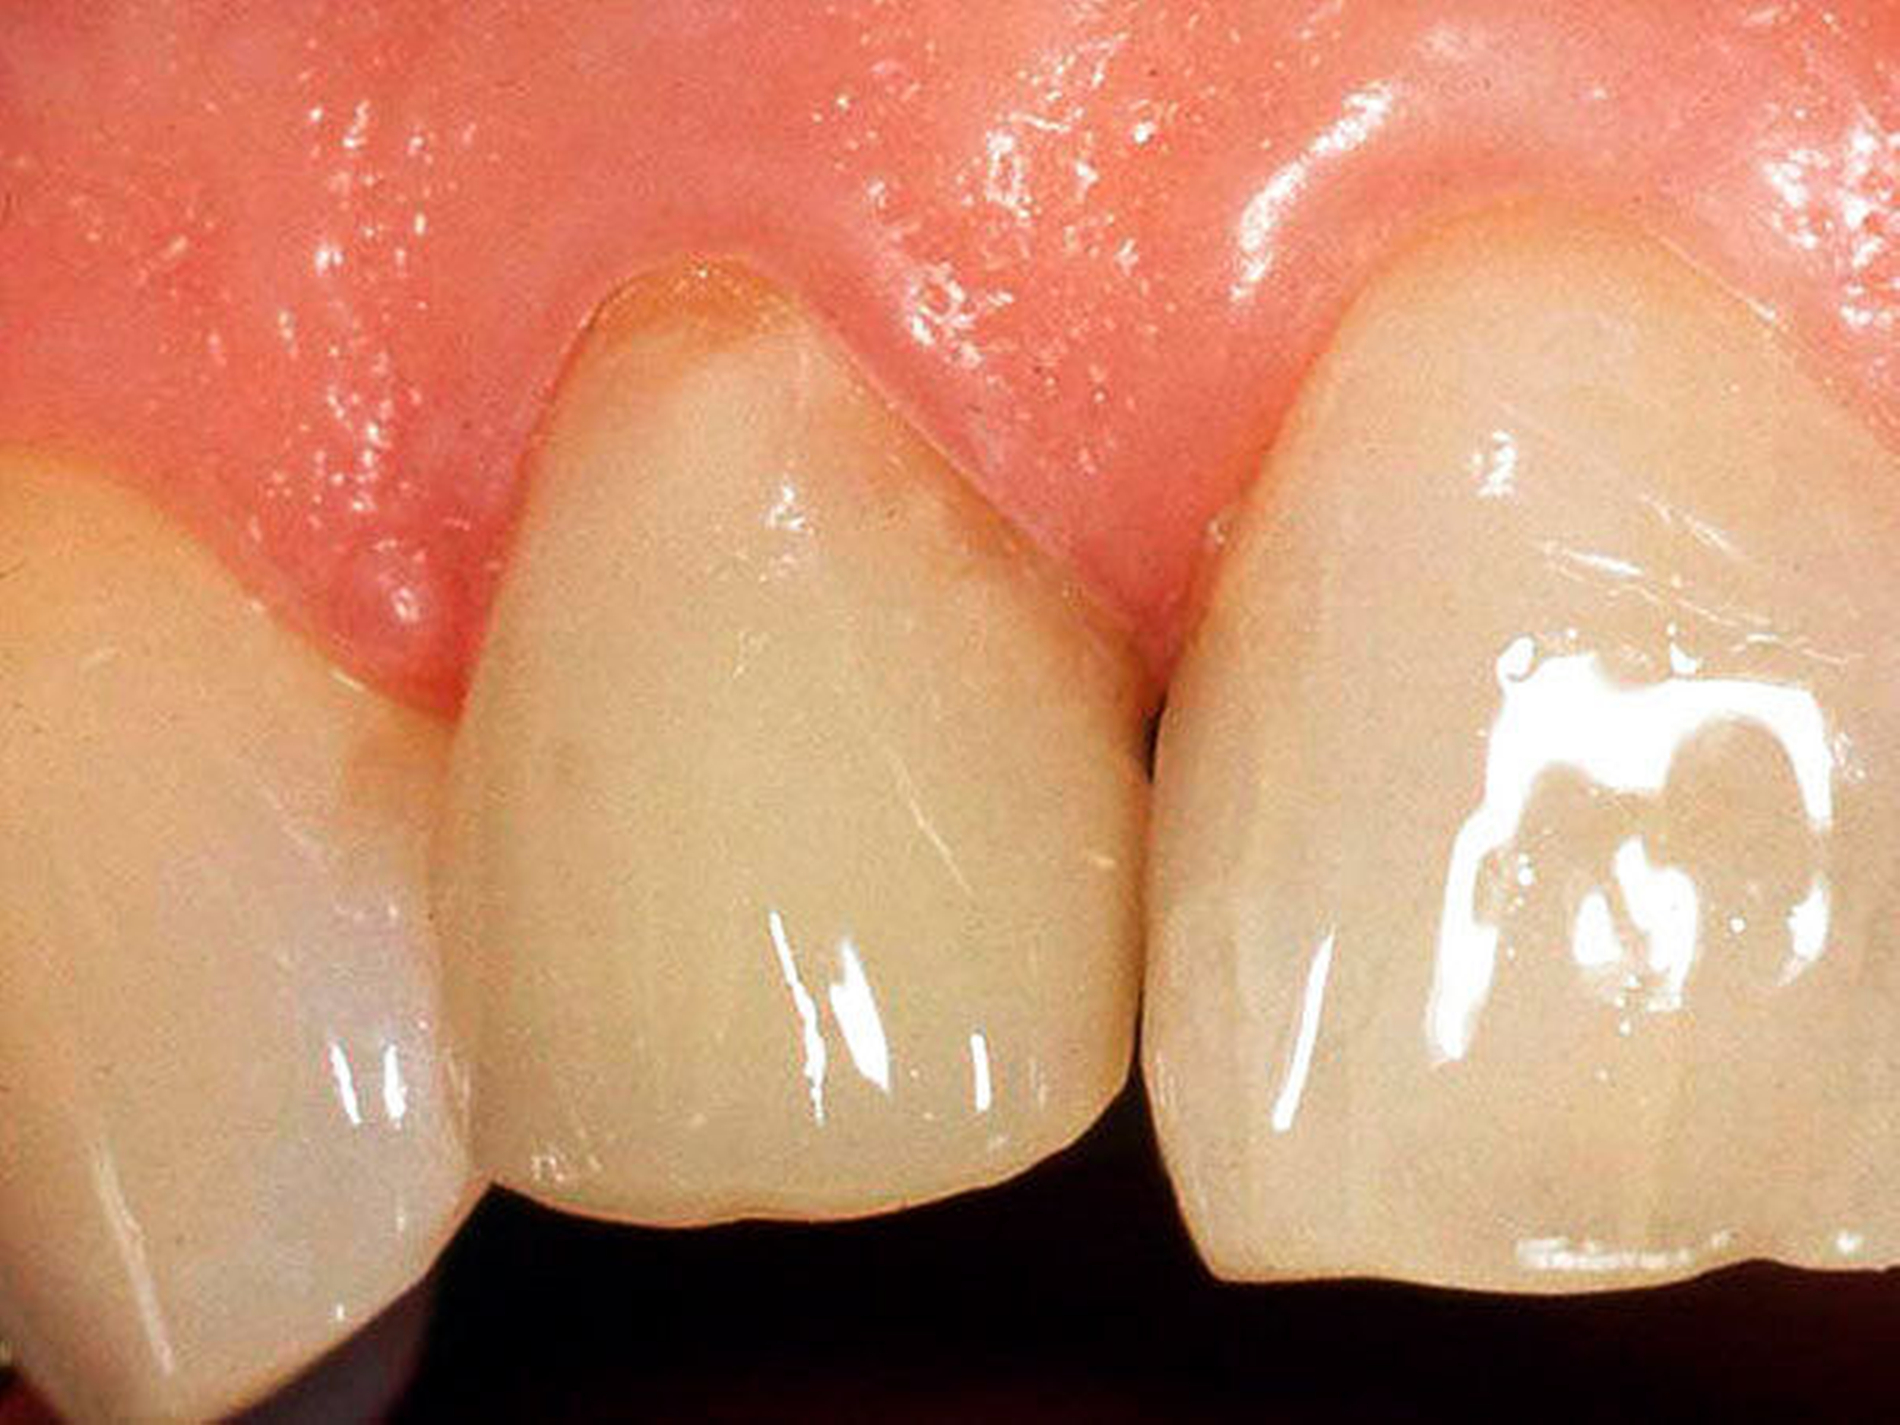

Abbildung 1a bis 1f: Direkte Überkronung im Frontzahnbereich (R1-Technik)

In den Abbildungen 1 bis 3 werden Optionen für frugale Interventionen auf restaurativem Sektor aufgeführt. Es handelt sich um direkte Vollüberkronungen im Frontzahnbereich (hier: hergestellt in R1-Technik / einphasig) (Abbildung 1), direkte Teilüberkronungen im Seitenzahnbereich (hier: hergestellt in R1-Technik / einphasig) (Abbildung 2), Reparatur-Restaurationen im Seitenzahnbereich (hier: hergestellt in R2-Technik / zweiphasig) (Abbildung 3). Technische Einzelheiten zur Vorgehensweise und den Ergebnissen sind an anderer Stelle beschrieben (Literatur siehe oben).

Durch die Erfolge der Adhäsiv- und Komposittechnik kann heute folgendermaßen vorgegangen werden:

Verzicht auf Wurzelkanalbehandlung / Erhaltung der Vitalität des Zahns

Verzicht auf Wurzelkanalstift

direkte minimalinvasive Kompositkrone (Verzicht auf indirekte Vorgehensweise)

Schonend: Die oralen Strukturen werden geschont und die Versorgung ist hinreichend stabil. Durch den Verzicht auf Wurzelkanalstifte wird das Wurzelfrakturrisiko reduziert. Zudem können Material-, Geräte- und Personalressourcen aus Praxis und Techniklabor, die beim klassischen Vorgehen anfielen, reduziert werden.

Bezahlbar: Hier ist anzumerken, dass die Kosten unter anderem von der zahnärztlichen Expertise abhängig sind: Zahnärzte, die mit direkten Restaurationen große Erfahrung haben, können zügiger und mit besserem Erfolg arbeiten als Kollegen mit geringerer Erfahrung auf diesem Gebiet; die Behandlung ist gleichwohl anspruchsvoll und deshalb nicht „billig“. Eine direkte Vorgehensweise kann, muss aber nicht automatisch zeit- und kostensparender sein als eine Versorgung mit indirekt hergestellten Werkstücken.

Gut genug: Ästhetische Feinheiten lassen sich bei direkten Restaurationen nicht immer in gleicher Perfektion einarbeiten wie bei indirekt gefertigten Kronen, auch die Stabilität des Hochglanzes lässt bei einigen Kompositpräparaten noch zu wünschen übrig. Andererseits erlauben die direkten Verfahren inzwischen mitunter sehr flexible Vorgehensweisen, die sich auch mit Farb- und Formkorrekturen von Zähnen kombinieren lassen. Die Erwartungen eines großen Teils der Patienten werden hinreichend erfüllt und die Nutzen-Risiko-Relationen wie auch die Aufwand-Kosten-Relationen erscheinen – wenn auch nicht durchgängig – so doch zumindest in vielen Fällen günstig.